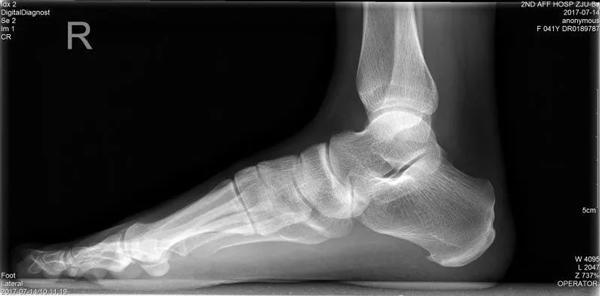

Cô Lí, nay 54 tuổi từng là giáo viên dạy tiếng Anh tại trường trung học. Từ khi còn nhỏ cô đã có một “bàn chân bẹt” – tức là gan bàn chân phẳng lì, không có vết lõm vòng cung như mọi người.

Dù đã tới nhiều bệnh viện để kiểm tra và điều trị nhưng cơn đau của cô Lí vẫn không thuyên giảm, cho tới khi cô gặp được bác sĩ Miêu Húc Đông. Bác sĩ Miêu đã tiến hành kiểm tra bàn chân cô Lí và phát hiện cô bị “hội chứng bàn chân bẹt” vì thường xuyên đứng lâu, đi giày cao gót.

Bàn chân bẹt, gan chân phẳng lì là một dạng dị tật phổ biến trên thế giới, gây ảnh hưởng nghiêm trọng đến thần kinh cột sống.

Tất cả trẻ sơ sinh đều có bàn chân không có vòm, hay còn gọi là bàn chân bẹt. Khi trẻ đến độ tuổi từ 2 đến 3, vòm bàn chân được hình thành. Cùng với hệ thống dây chằng, vòm bàn chân giúp cho chúng ta có thể chịu lực, cân bằng, đi đứng nhẹ nhàng, giúp giảm phản lực từ mặt đất dội lên khi chân di chuyển. Thông thường, những ai có hệ thống dây chằng quá lỏng lẻo sẽ dễ bị bàn chân bẹt. Đó là vì các xương ở bàn chân không được cố định tốt.

Bàn chân bình thường.

Bàn chân bẹt.